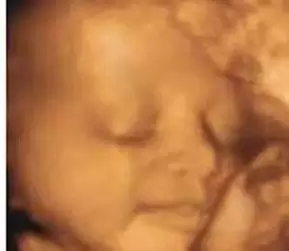

令人心动的四维彩超图,麻麻看着就笑了~

宝宝四维彩超图像,非常有趣和可爱,看到这些健康的宝宝,再累也值了。❤❤❤

甜甜的笑,美梦不错哦~